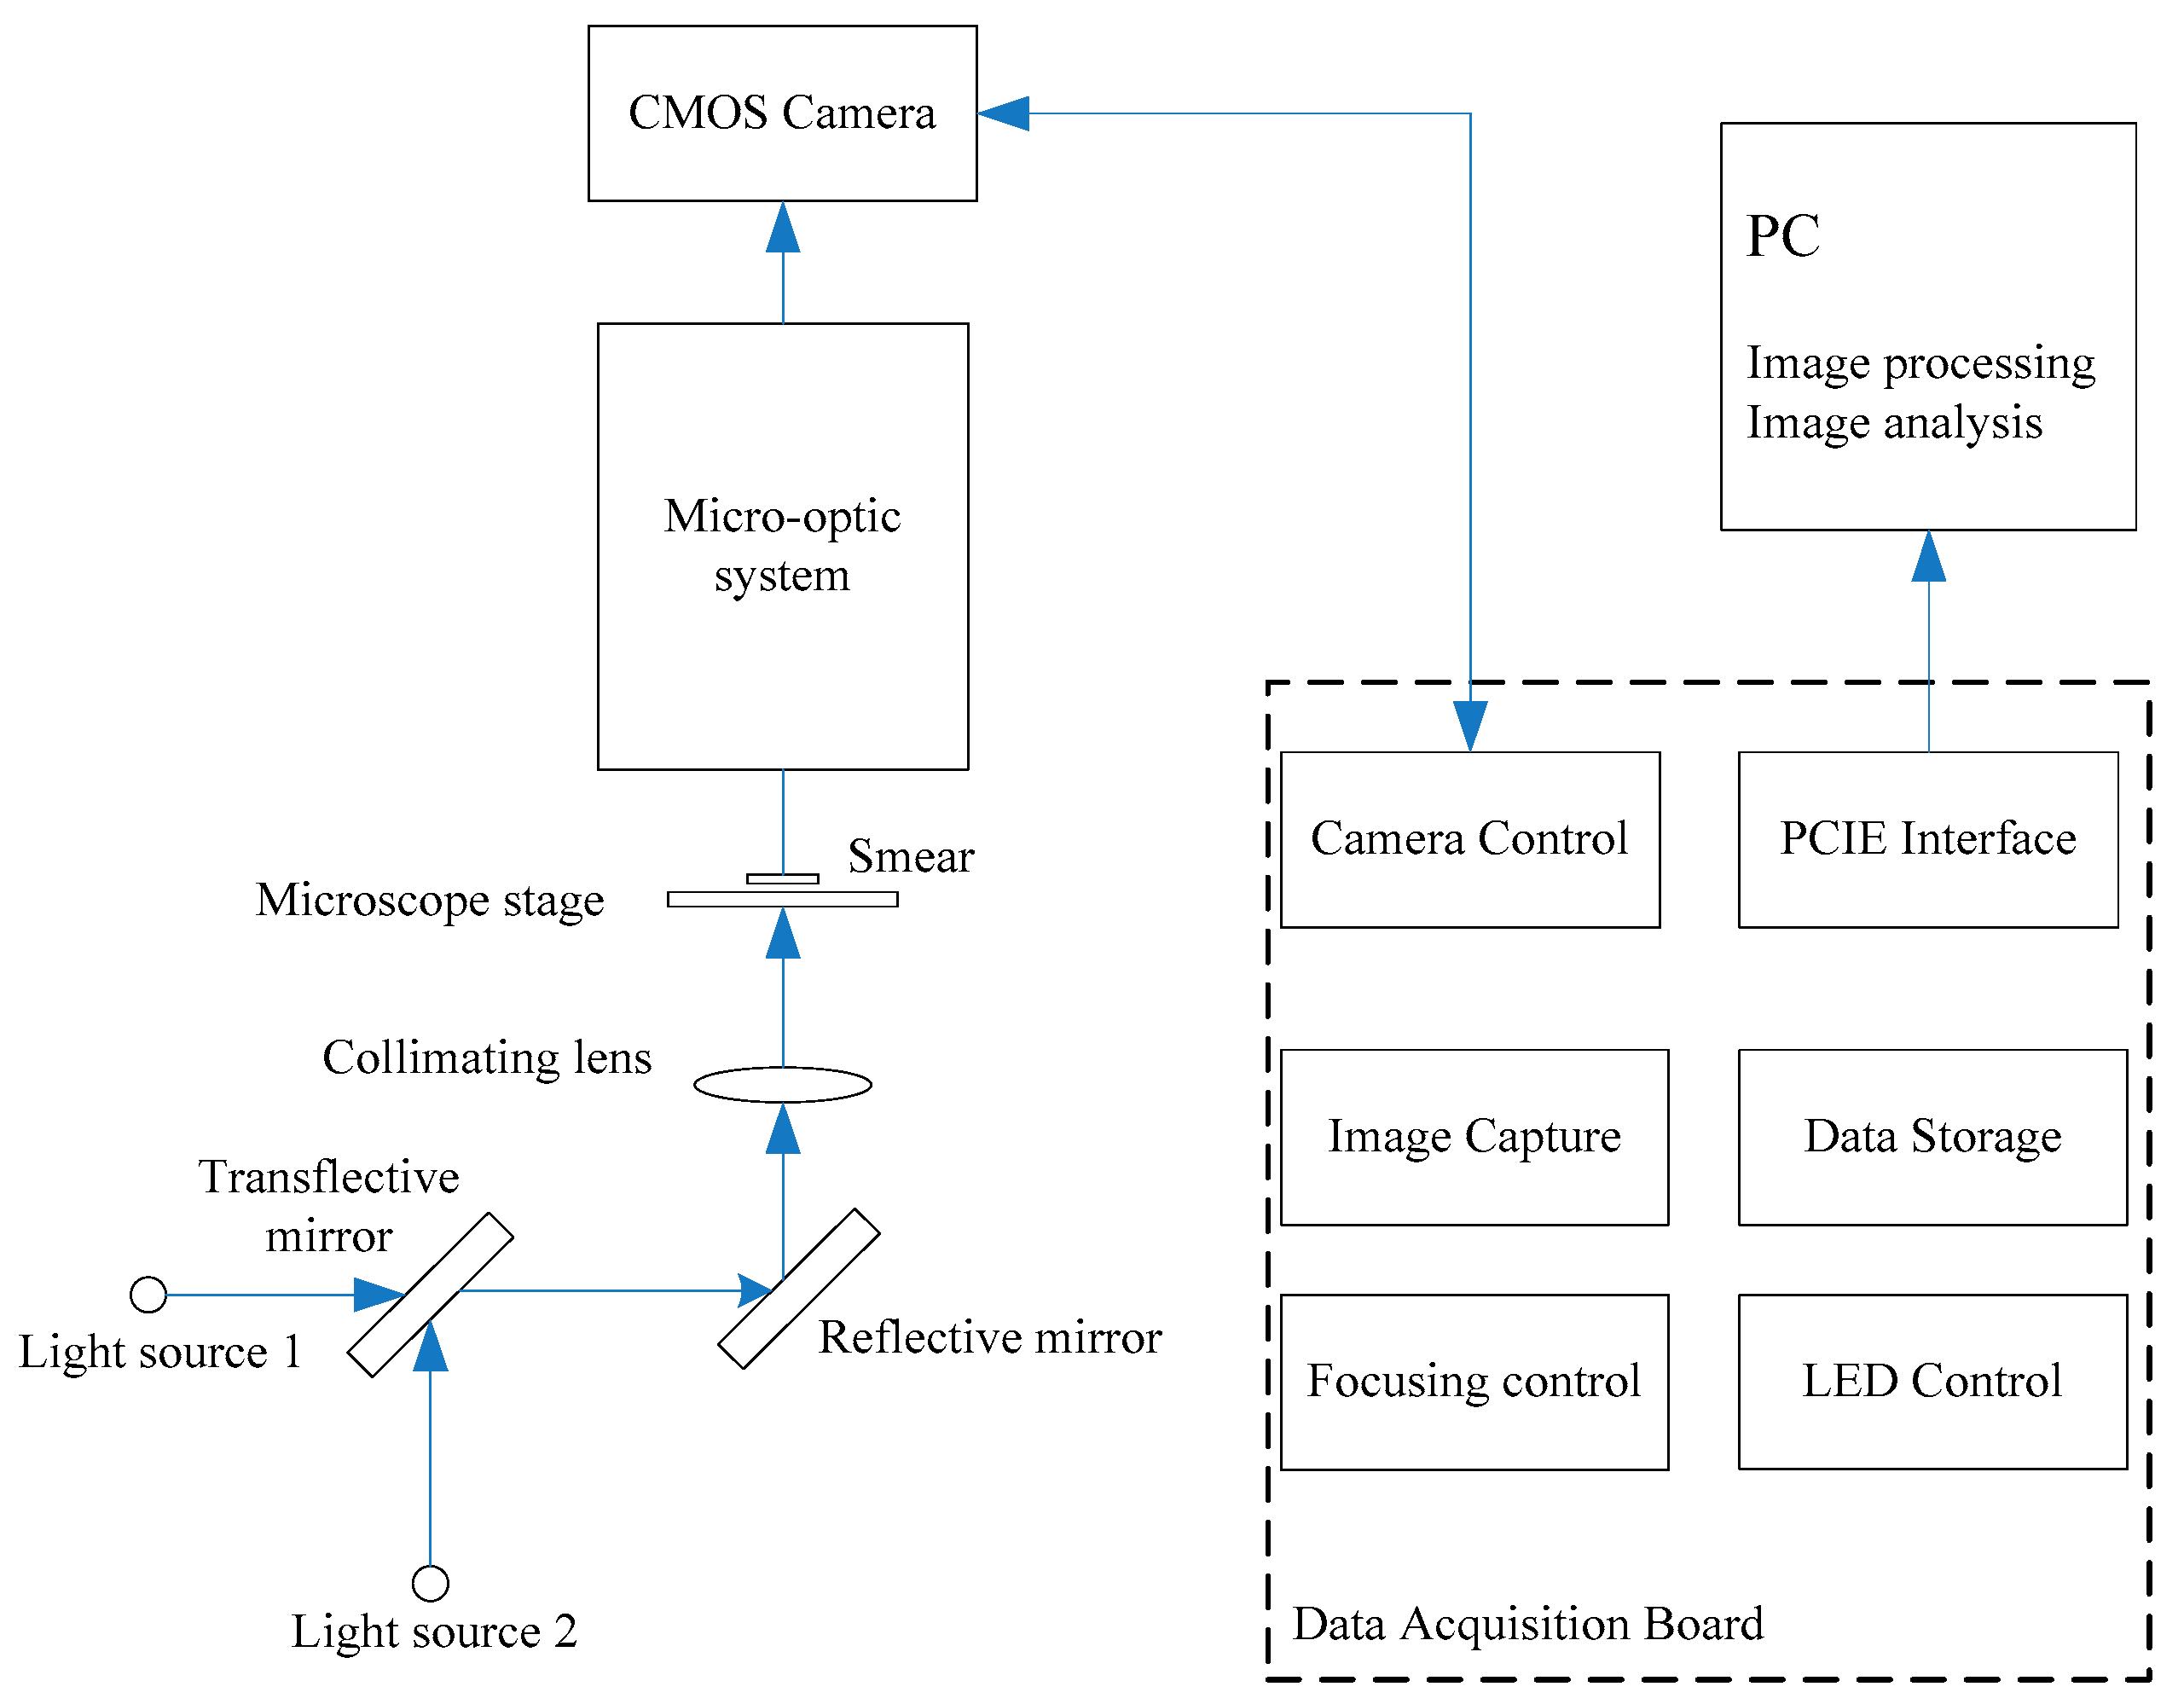

2. Design and Principle

2.1. Design of Microscopic Multi-Spectral Imaging System